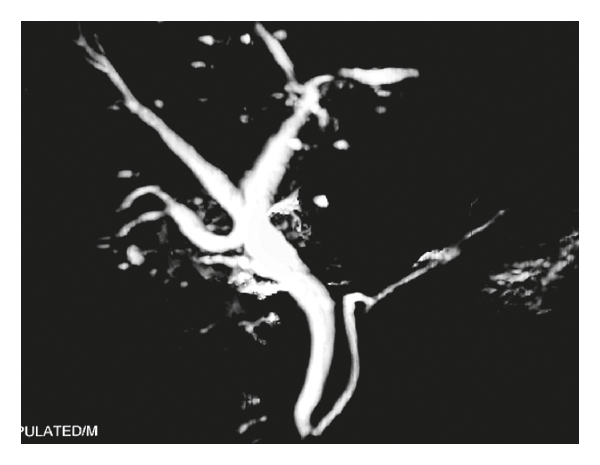

Ten (55.5%) among 18 patients required surgical intervention. There were seven Roux-en-Y-hepaticojejunostomy (Hepp-Couinaud approach) by the experienced hepatobiliary surgeon, five delayed and two performed intraoperatively. One patient required end-to-end common bile duct repair over the T-tube (detected intraoperatively) for complete transection without segment loss during open cholecystectomy. The remaining 2 patients required emergency laparotomy, peritoneal lavage, and drain placement for peritonitis due to the class A Strasberg injury (confirmed by postoperative MRCP) (Figure 2). Postoperatively, two patients developed superficial surgical site infections (SSIs). There was no mortality in our series of patients (Table 2). The median length of hospital stay postcholecystectomy was 8 days (range: 5–28 days). There was no restricture at a median follow-up of 13 months (range: 8–36 months), as confirmed by history and clinical examination, liver function tests, and ultrasonography (Table 3). When the trend of injuries was compared, there was a significant decrease in incidence (0.21% vs. 0.68%; ) of major bile duct injury at index hospital (Table 4).